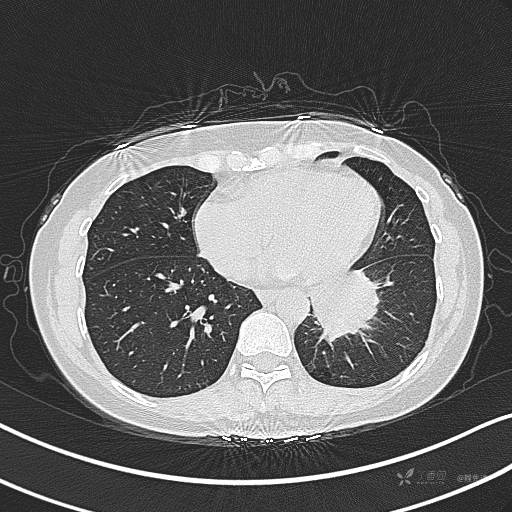

CT平扫

肺窗